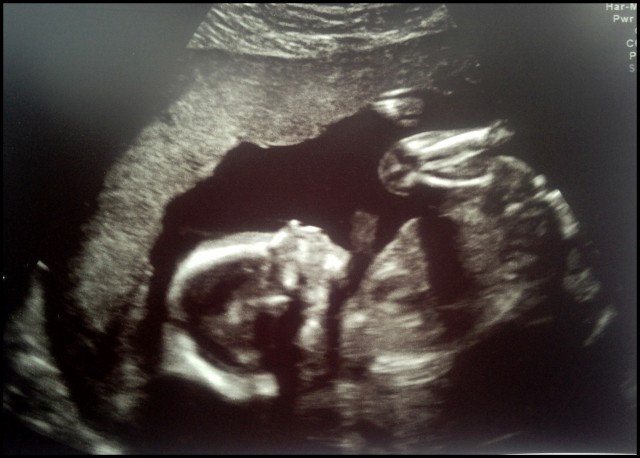

I tisdags var vi på Helsingborg lasarett kl 7.30. På ultraljudsavdelningen… Nu förstår jag vad alla blivande föräldrar pratar om.. Att se sitt barn i magen.. overklig känsla.. den var så fin och hel och riktig och det lilla hjärtat som slog och alla detaljer som syntes… som hjärtkammare och hjärnhalvor.. de små fingrarna och fötterna.. Allt syntes väldigt tydligt och den var hemskt livlig.. inte stilla en sekund…♥